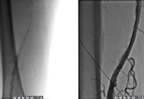

Radiotezlikli obliterasiyaların nəticələri